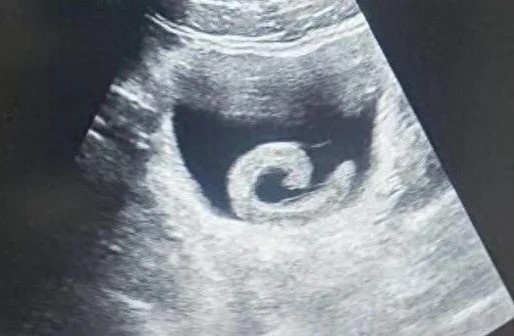

Hình ảnh siêu âm cho thấy một con đỉa sống trongbàng quang của người đàn ông ở Trịnh Châu, Trung Quốc, trước khi được các bác sĩ tiến hành phẫu thuật lấy ra. Ảnh: O.C

Con đỉa đã gây ra cho Zheng những cơn đau dữ dội đến mức anh không còn lựa chọn nào khác ngoài việc đến phòng cấp cứu của một bệnh viện địa phương. Khi nghe lý do, các bác sĩ không khỏi sửng sốt. Kết quả siêu âm xác nhận đúng như anh trình bày: một con đỉa sống đang ở trong bàng quang. Ngay lập tức, các bác sĩ chuẩn bị cho ca phẫu thuật khẩn cấp nhằm loại bỏ ký sinh trùng và cứu mạng bệnh nhân.